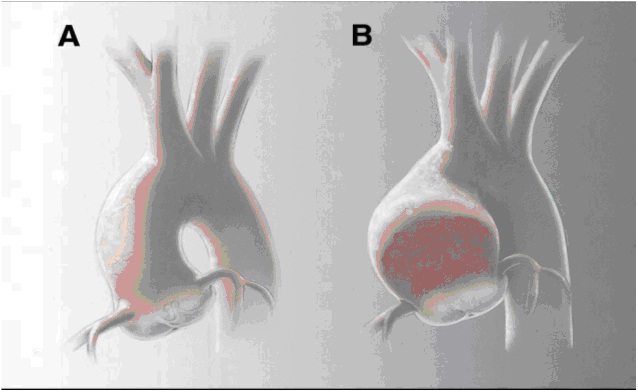

(A) Aorta Normale (B) Aorta Dilatata

Sacciformi: la dilatazione interessa un segmento del vaso, la cui parete si estroflette formando una sacca, generalmente occupata da trombi, che comunica con il vaso attraverso un orifizio chiamatocolletto.

Fusiformi: la dilatazione coinvolge il vaso in tutta la sua circonferenza.